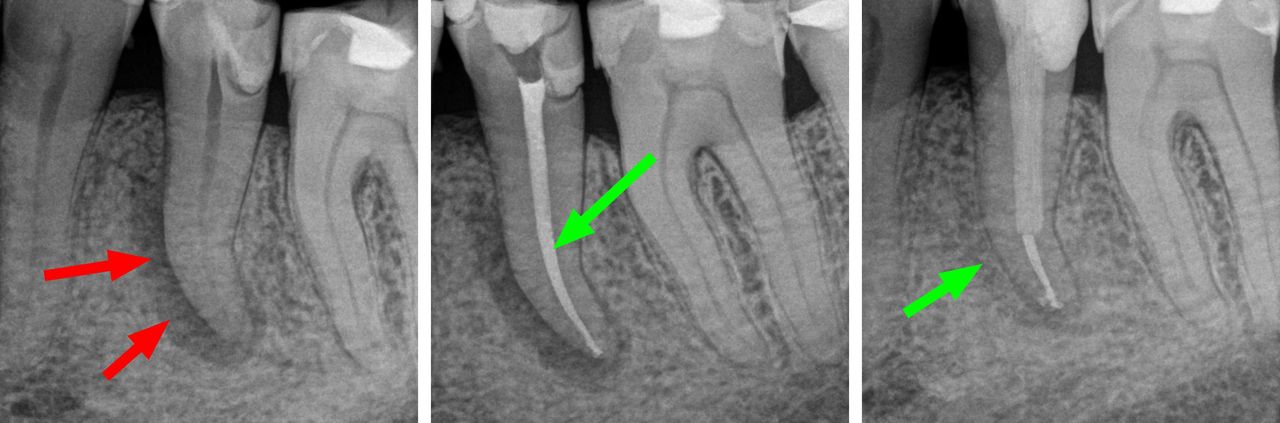

- Usuwanie złamanych narzędzi kanałowych oraz innych ciał obcych pozostawionych w kanałach korzeniowych

- Specjalizujemy się w powtórnym leczeniu kanałowym i leczeniu powikłań co oznacza, że mamy wieloletnie doświadczenie w usuwaniu złamanych instrumentów kanałowych w szybki, bezbolesny i nieinwazyjny sposób. Dr Gończowski jest autorem specjalistycznego zestawu mikroinstrumentów (FRS®) przeznaczonych do usuwania ciał obcych z kanałów korzeniowych